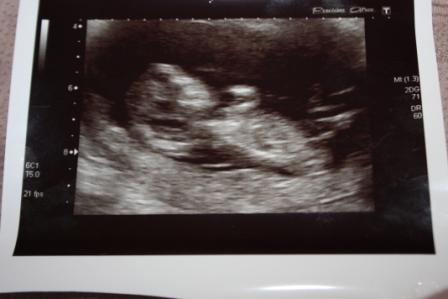

Is that the nub then that I can see in the scan pic? and not the cord?? Thought it seemed a bit big at first but later when I searched google images for boy nubs there were plenty similar that came up!

If that's the nub then I guess boy but really not sure if that's the nub or not :/

I', gonna have to be different and guess girl, looks pretty long and it reminds me of my girl pic in the confirmed section, wouldnt be suprised if I was completely wrong though:bigsmile:

Guessing boy :) first pic looks like the nub on an angle

Looks like a boy due to the angle of the nub :)